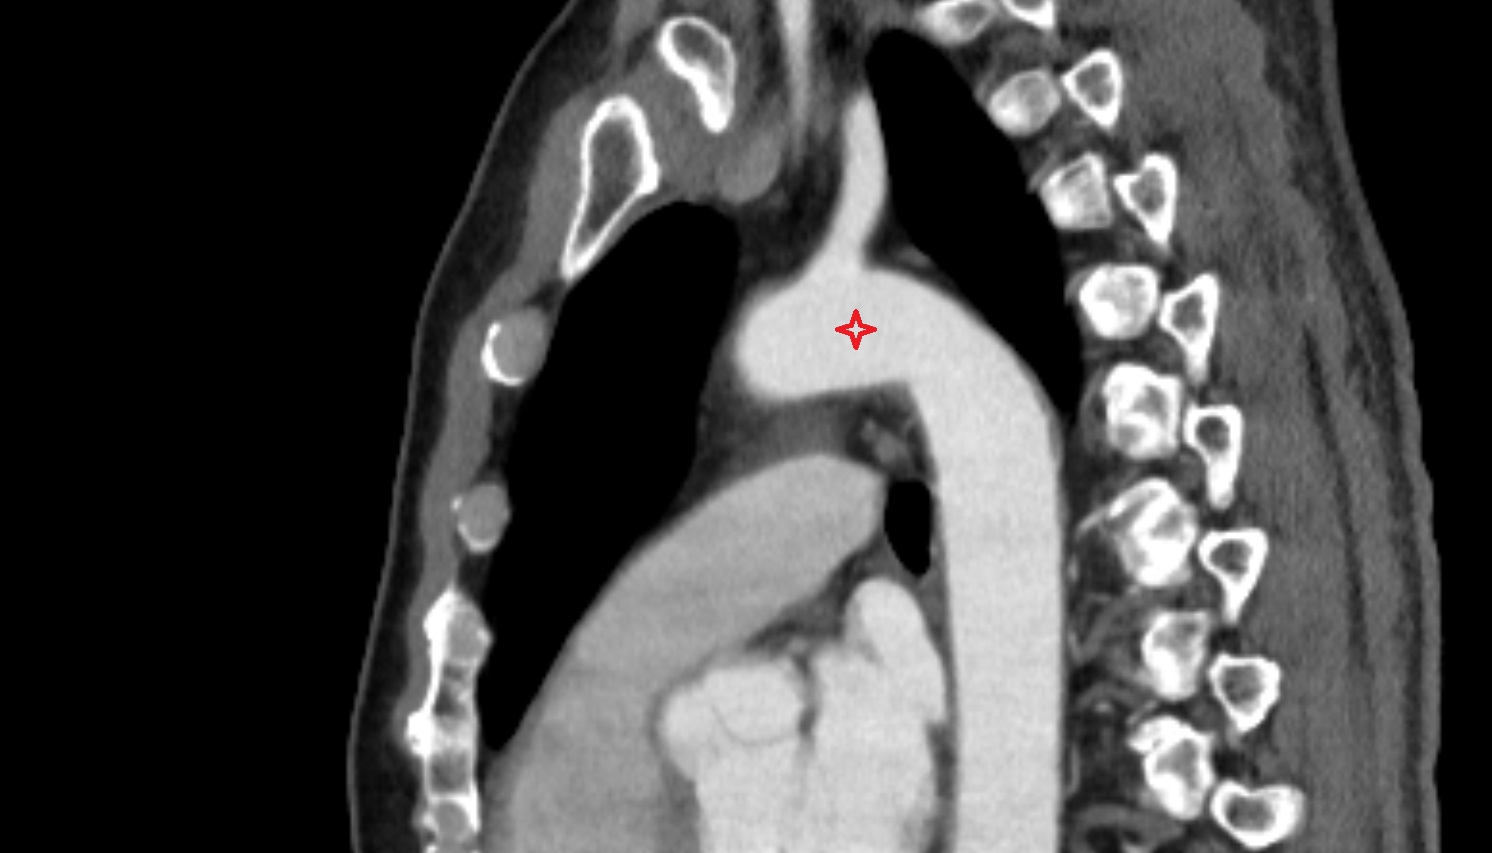

- Ascending aorta

- Arch of aorta

- Descending thoracic aorta

- Pericardium

- Heart

- Trachea

- Thoracic part of esophagus